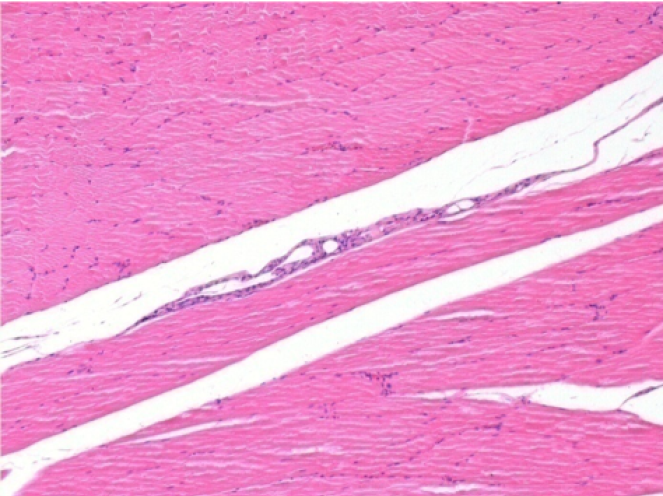

L:Pretibial-No treatment

10 days after Endopeel Injection 0.1ml in the right pretibial muscle.

Here you may see the formation of the vacuoles which are surrounded by lymphocytes. Vacuoles are different from tissue necrosis . The presence of lymphocytes is related to the permeability of the cell membranes.